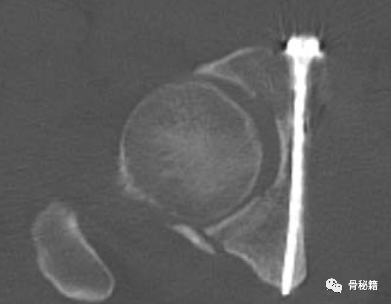

螺钉宽度

其髋臼内缘最狭窄处即为可通过螺钉的宽度。

该螺钉的特点是通过前方固定髋臼方形区及后柱。